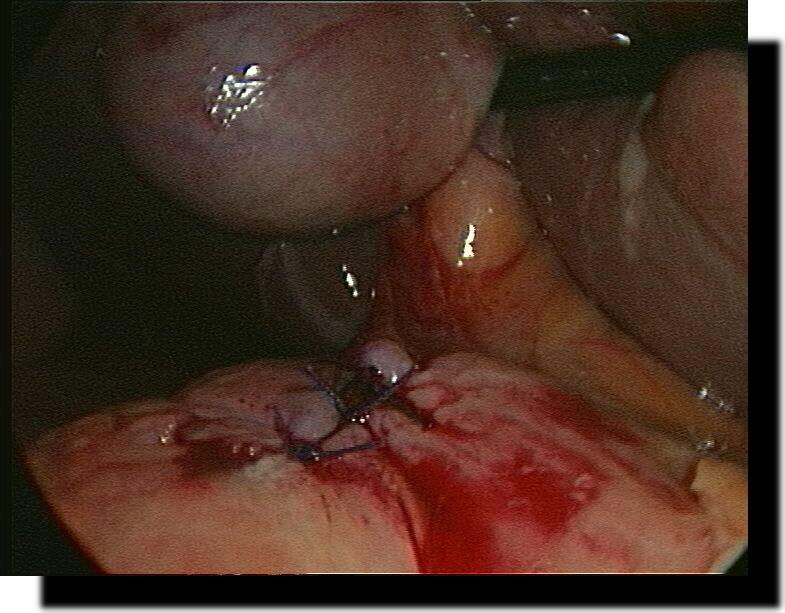

Magenperforation

Z.n. laparoskopischer Ulcusbiopsie und Magenperforations-Übernähung